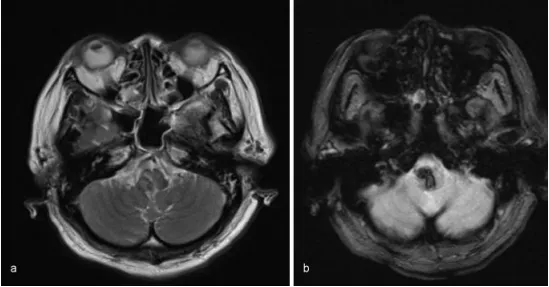

MRI检查未发现明确出血原因,既无海绵状血管瘤也无动静脉畸形,最终确诊为高血压原发性延髓出血。持续降压药物治疗使血压逐步下降,但呼吸抑制症状未见改善。

磁共振图像显示出血灶无明显病理原因:(a)T2加权序列;(b)T2加权序列。